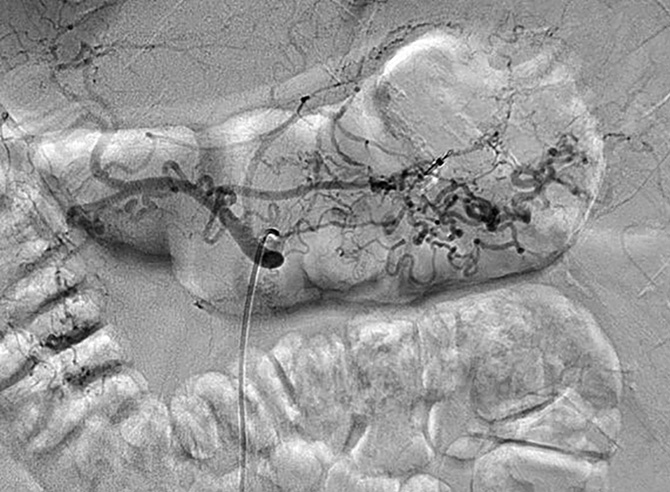

A 55-year-old male patient arrived at the Emergency Department of the Republican Vilnius University Hospital complaining of black stools and general weakness for only 1-day, tachycardia and low arterial blood pressure. UGIB was suspected. An extra esophagogastroduodenoscopy was performed. Arterial bleeding was observed from the posterior stomach wall in the border of the body/upper third of the stomach (Figures 1, 2). No pathological formations were visible in the mucosa. Dieulafoy’s lesion was suspected. The abdominal surgeon/endoscopist immediately started to stop the bleeding with adrenaline injection, but it was not enough. When we used endoscopic clip (Figures 3, 4). Bleeding was completely stopped. Patient’s condition was stabilized. But disease remained unknown. In order to reduce the risk of recurrent bleeding, we performed selective angiography of truncus coeliacus and embolization of the distal branches of arteria gastrica sinistra and some arteria lienalis branches, that feed formation through collateral blood flow (Figure 5). Large microspheres and pushing spirals were used for embolization (Figures 6, 7). The cause of bleeding still remained surely unknown. Now we suspected tumor. Only after by detailed strict anamnesis based on the patient’s life history, we conclude that the patient has a genetic disorder – Grönblad-Strandberg syndrome. According to our data, only four people suffer from this syndrome in Lithuania. Adjacent to this the patient had been operated for rectal cancer in the past, followed by ileostomy closure and abdominal wall hernioplasty for postoperative hernia. It is currently known that the patient has metastases in the liver and brain. The spread of cancer metastases, wide and severe comorbidities worsen the patient’s current condition, but despise these severe illnesses after proper and timely interventions, the patient lives without recurrent bleeding until now.

Figure 5. Selective truncus cealicus angiography